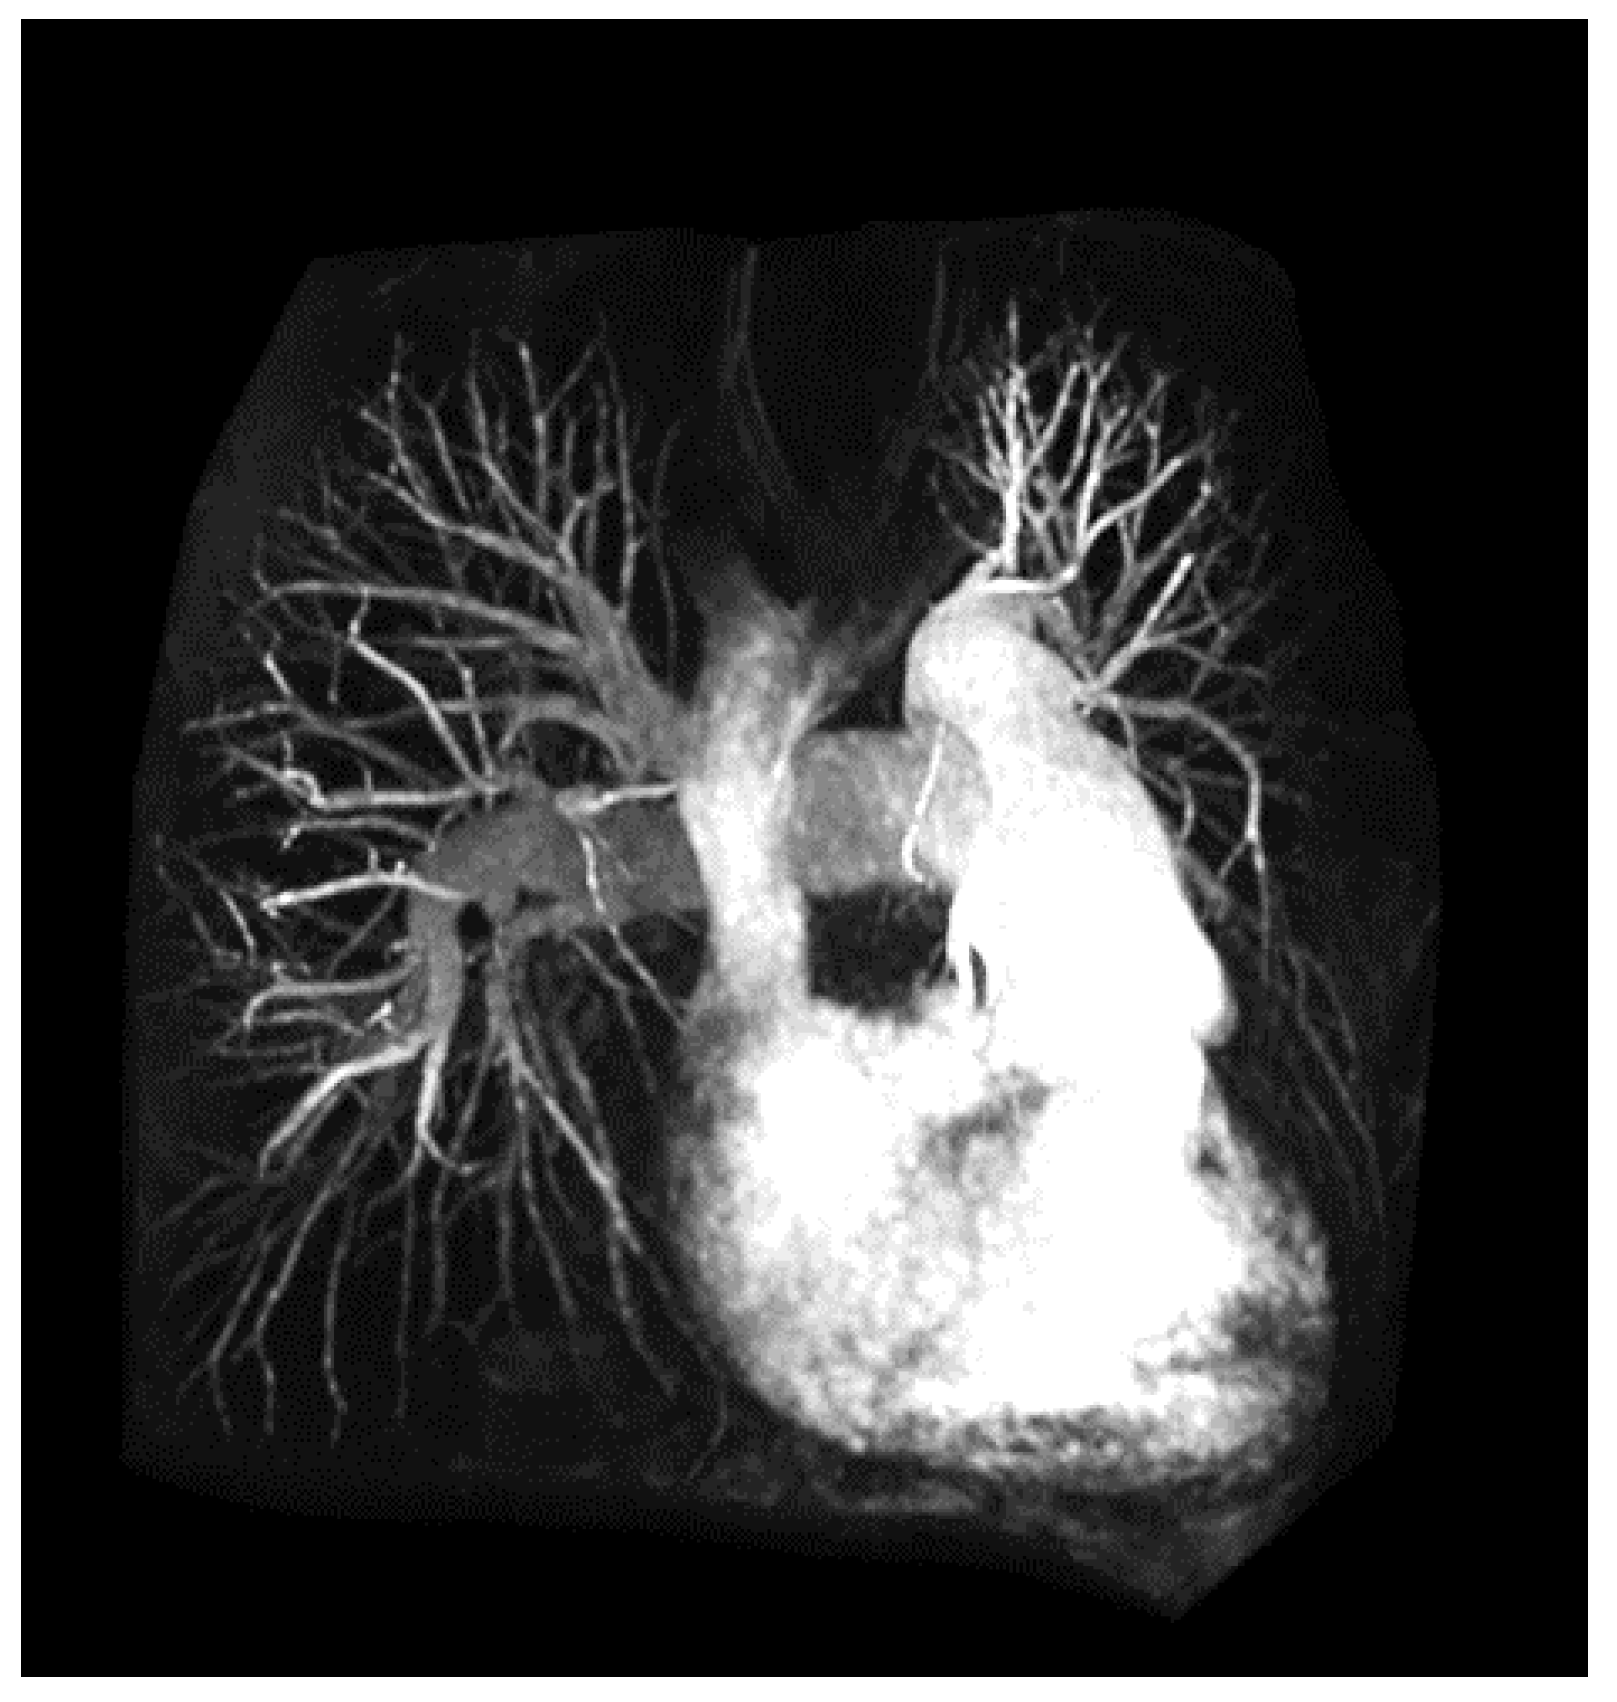

2.3. Angiography